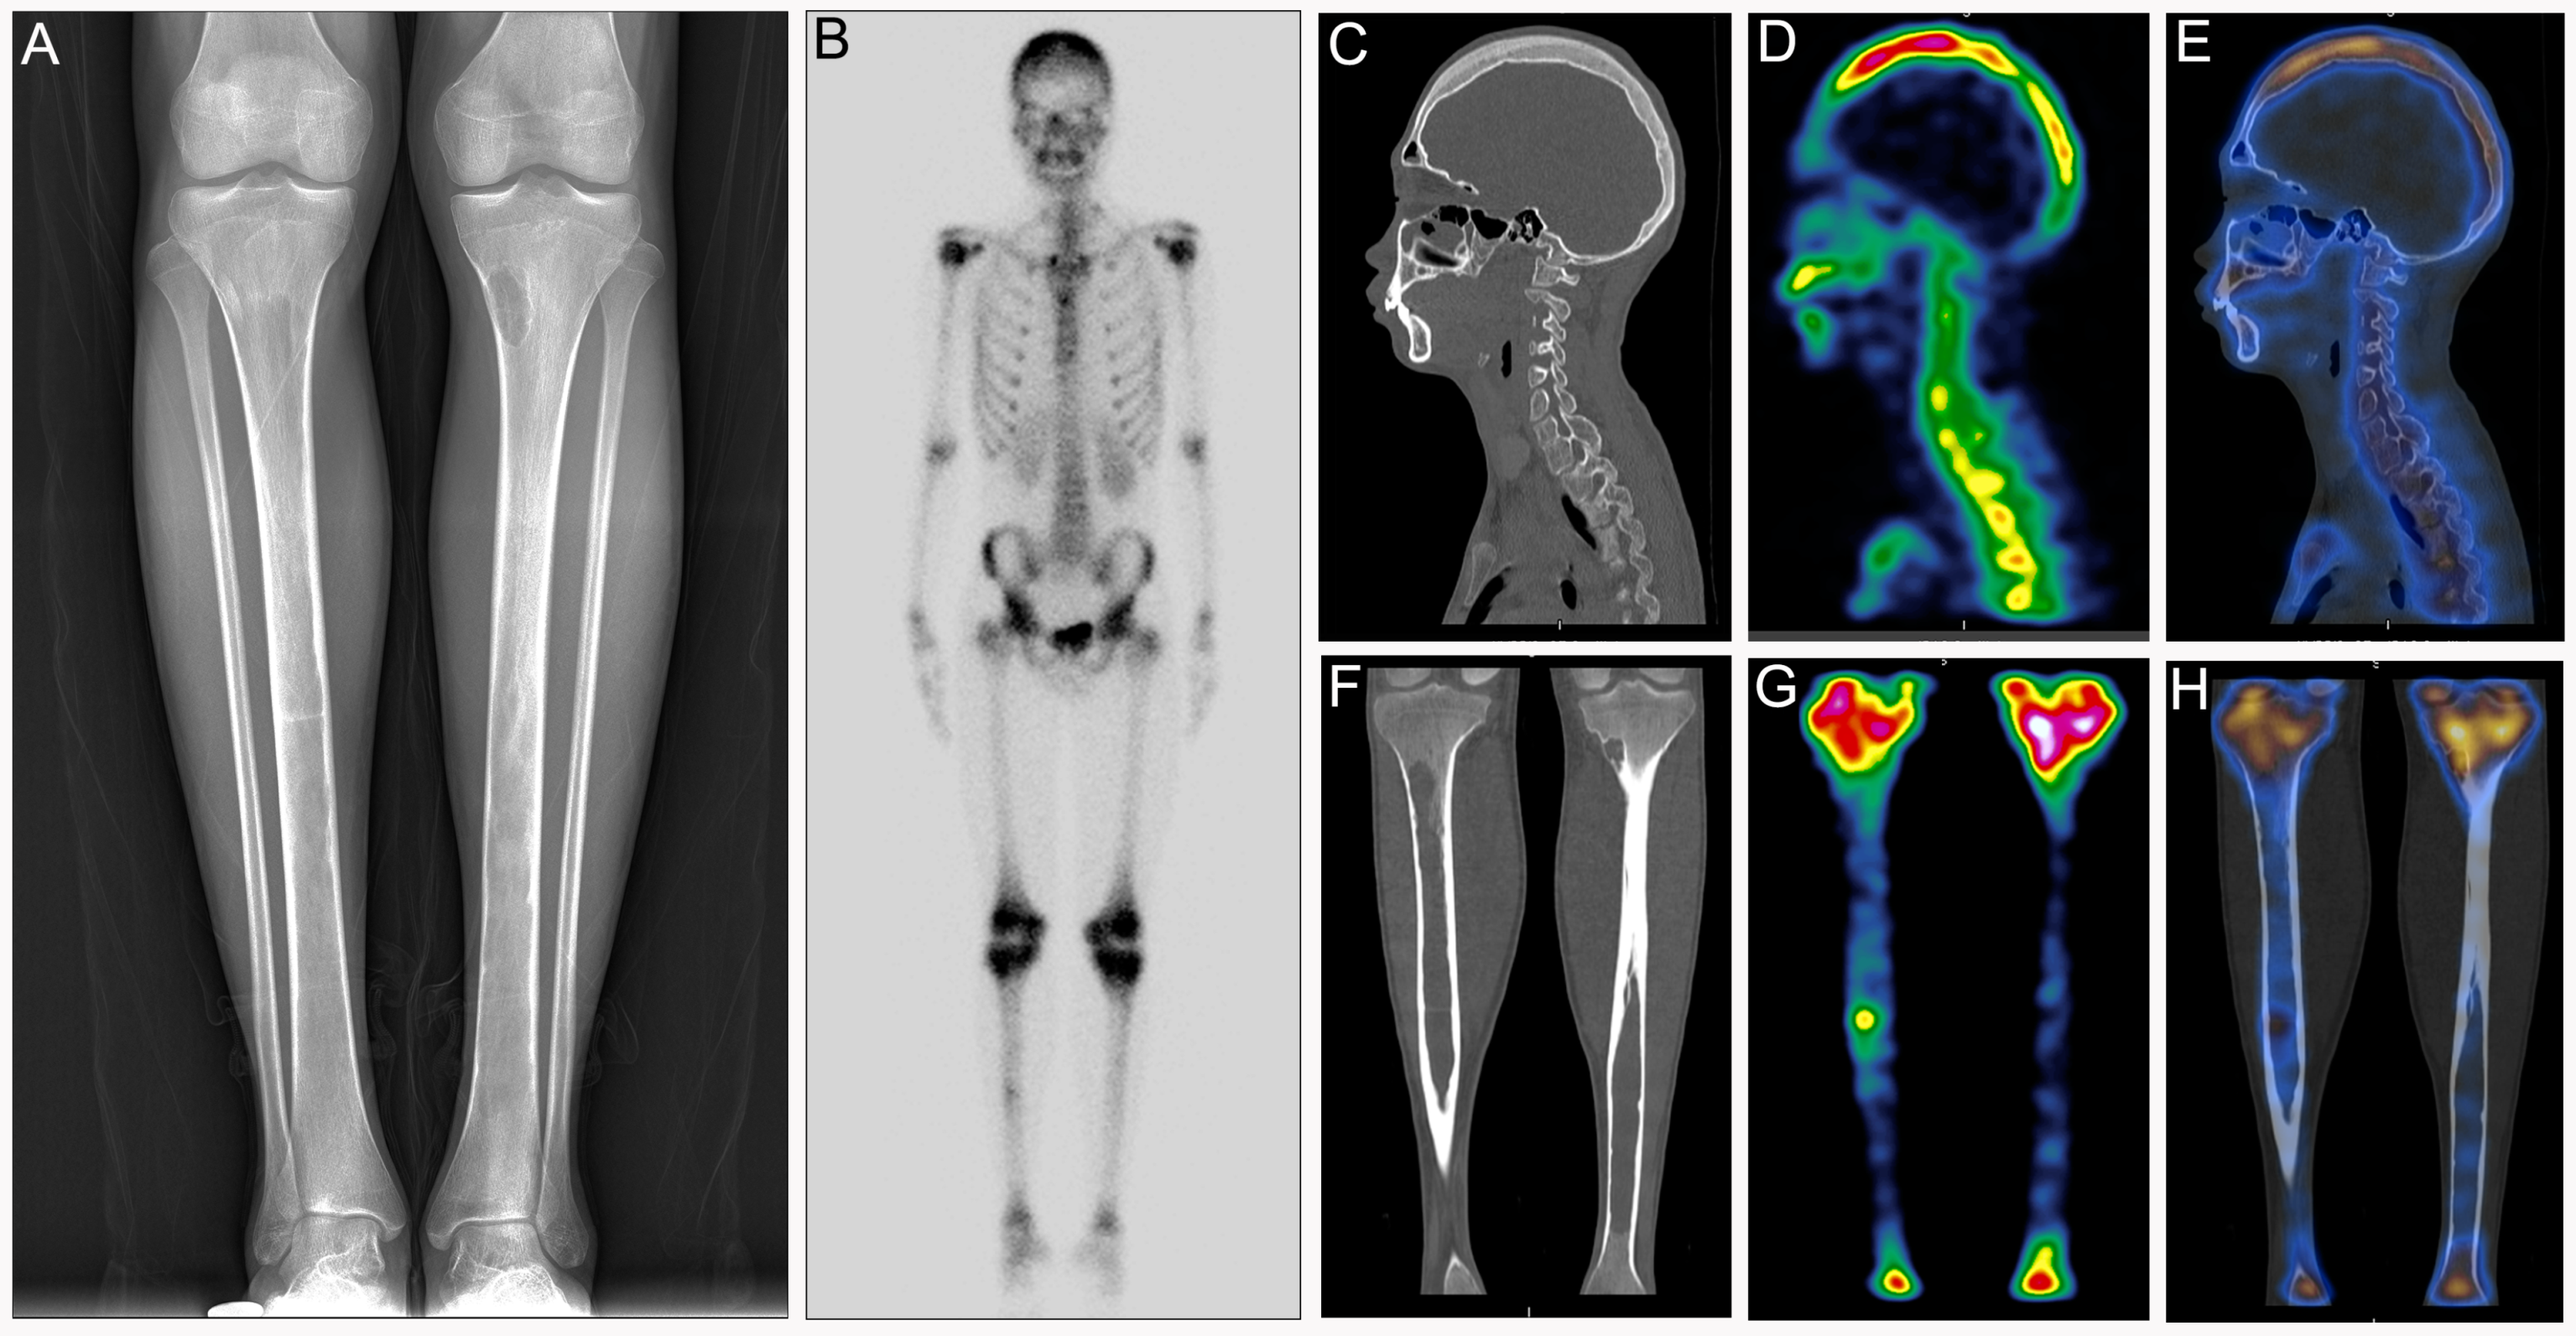

Diagnosis of Bone and Joint Disorders: Resnick, Donald, Differential Diagnosis of Rare Diseases Involving Bilateral,

Differential Diagnosis of Rare Diseases Involving Bilateral, Differential Diagnosis of Rare Diseases Involving Bilateral,

Differential Diagnosis of Rare Diseases Involving Bilateral, Lubbock Spine Institute Joint Disorders - Lubbock Spine,

Lubbock Spine Institute Joint Disorders - Lubbock Spine, Differential Diagnosis of Rare Diseases Involving Bilateral,

Differential Diagnosis of Rare Diseases Involving Bilateral, Most Common Bone Diseases,